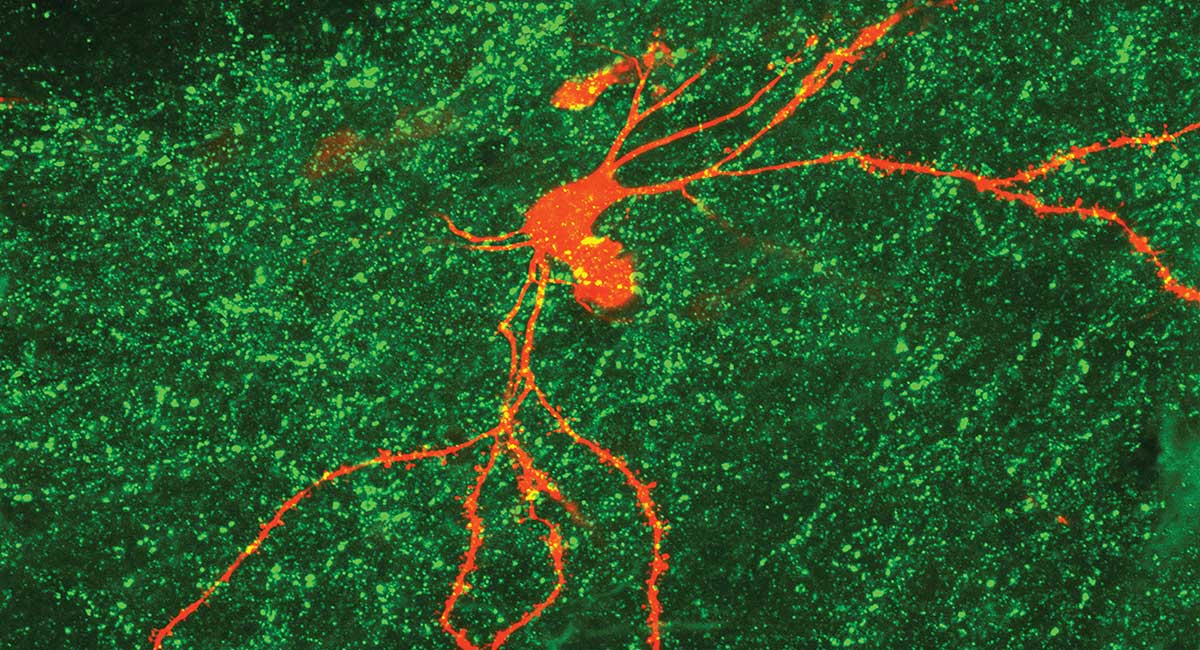

Neurons in the hypothalamus responsible for regulating the body's circadian rhythms.

Porcu is studying the effects of circadian rhythms, including their effects on administering medications at optimal times of day for maximal efficacy. She also studies how blue light emitted from screen devices affects the adolescent brain.

Porcu is using rodent models to study how nocturnal blue light exposure affects stress and anxiety levels in the adolescent brain. Blue light emitted from screen devices — particularly phones and laptops — adversely affects mood, cognition and sleep when the exposure occurs after sunset, a function of circadian rhythms.

“Cells in the back of our retina are very sensitive to the blue wavelength, and they activate brain regions that are not supposed to be active at night. This is what leads to problems in the development of the neural circuit during adolescence,” says Porcu, adding that research has shown dramatic increases in adolescent anxiety since the advent of smart phones in 2008.

Porcu’s team uses a technique called fiber photometry, inserting optical fibers in a mouse’s brain to measure neuronal activity while exposed to different stimuli, including blue light. They also use molecular biology assays to screen for RNA and cellular proteins that change because of environmental exposure.